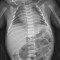

Seorang laki-laki usia 24 tahun mengalami kecelakaan tunggal saat mengendarai motor. Pasien mengeluh kaki kirinya nyeri dan memar, tidak ada luka terbuka. Hasil rontgen di IGD tampak proximal tibia compression fracture. Kemudian dilakukan tindakan ORIF untuk memperbaiki posisi tulang tibia.

Apakah sejawat pernah mendapatkan pasien serupa? Hasil rontgen seperti tidak ada patah tulang tapi ternyata ada patah tulang.

Saya terkecoh dok.. ga terlalu terlihat jelas ya patah nya.. Setelah liat foto after nya baru tau ada patah dstu..